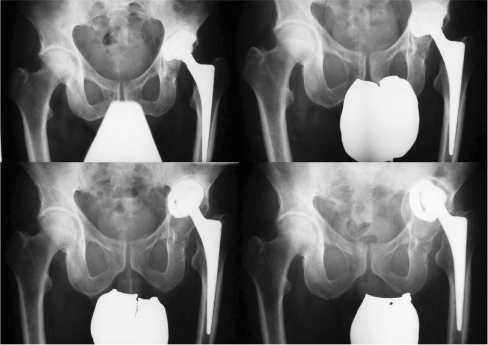

Surprisingly, aseptic loosening and migration did not lead to pain and impairment in many cases, even when massive bone loss was already evident. This scenario is particularly worrisome and, therefore, with this type of acetabular component, regular radiographic follow-up seems advisable to detect painless migration before severe bone loss can occur, necessitating more demanding revision surgery (Fig. 4).

Fig. 4.

Pelvic anteroposterior radiographs show fixation failure of a Mecring cup with continuous migration and massive bone loss. The patient noticed leg length discrepancy and only slight pain before revision surgery was performed